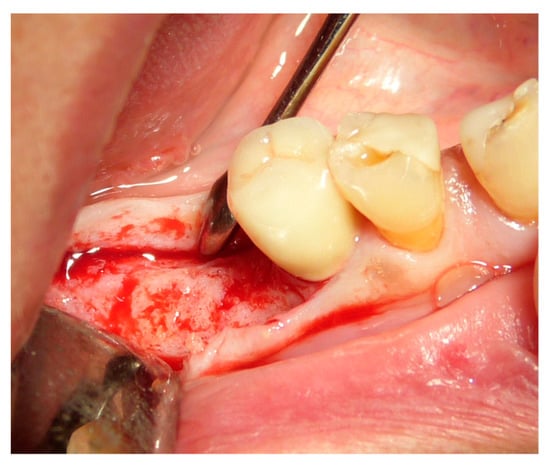

Figure 7. Dental element 46 to be extracted with the need for ridge maintenance due to an extensive interradicular defect.

Figure 8. Ridge maintenance through the use of the extracted element and cover with a resorbable membrane.